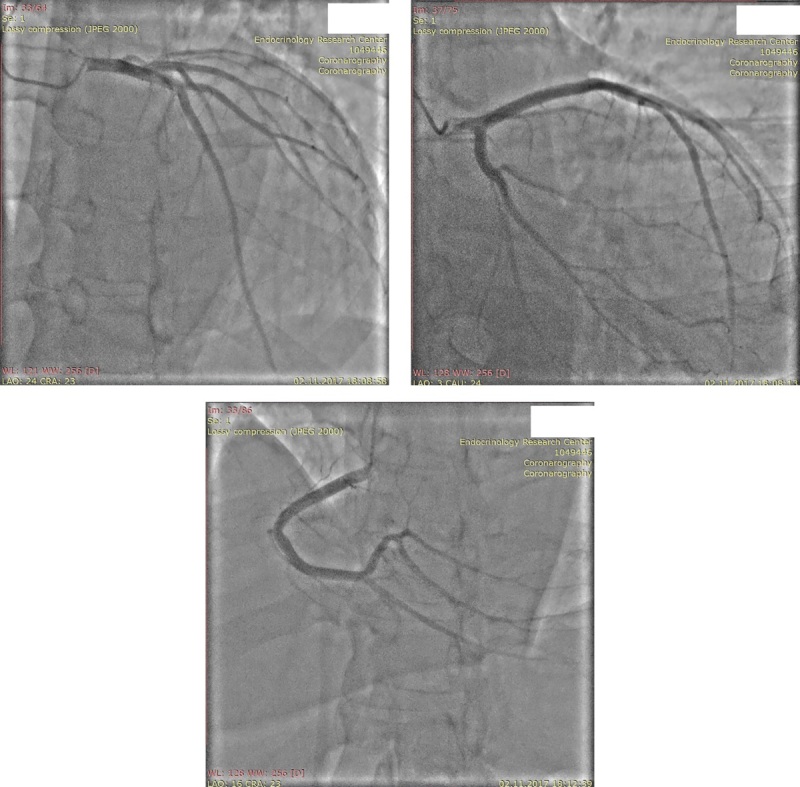

Cortisol-induced dilated cardiomyopathy (CI-DCM) is a rare manifestation of endogenous hypercortisolism (EH). Optimal management of patients with CI-DCM is a major challenge due to the rarity of the pathology and the lack of expert community guidelines. This article describes a case of successful management of a patient with ACTH-secreting pituitary tumor and CI-DCM.A 44-year-old patient was hospitalized with symptoms of chronic heart failure (CHF) and EH. The diagnosis of non-ischemic myocardial damage with phenotype of DCM was verified by echocardiography and coronary angiography. According to hormonal and imaging tests, and selective blood sampling from the inferior petrosal sinuses, an ACTH-secreting pituitary adenoma was diagnosed. A transnasal transsphenoidal adenomectomy was planned. Due to the symptoms of CHF and systolo-diastolic dysfunction of the left ventricle (LV), significantly increasing the risk of adverse perioperative cardiac events, the intervention was postponed. Stabilization of the patient's condition was achieved after 4-month therapy with use of betaAB, ACEI, MRA, diuretics, and steroidogenesis inhibitors. Stabilization of the patient's condition allowed to perform transnasal transsphenoidal adenomectomy without perioperative complications, with postoperative decrease of ACTH and cortisol levels. Follow-up examinations demonstrated preservation of eucorticism, regression of CHF symptoms. progressive decrease of LV size/volumes with increase of LVEF.Cortisol hypersecretion can damage myocardium with a phenotype of DCM, with symptoms of CHF being the dominant clinical manifestation of EH. The use of betaAB, ACEI, diuretics, MRA, and steroidogenesis inhibitors is reasonable to control symptoms of CHF and prepare a patient with CI-DCM for surgical intervention. After normalization of cortisol level, regression of CHF symptoms and significant reduction of heart chamber size/volumes with increase of LVEF are noted, which allows to conclude about reversibility of pathologic cardiac remodeling.